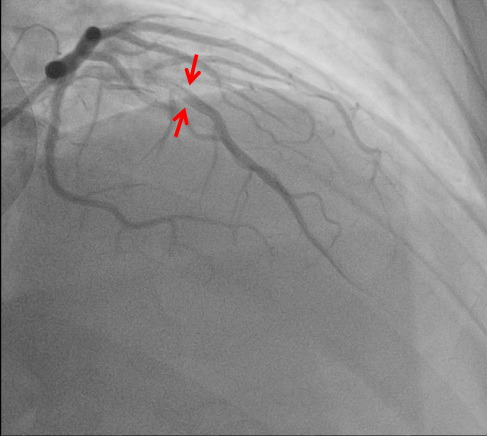

秉持着“时间就是心肌,时间就是生命!”的原则,心血管内科团队迅速到位,在与患者家属进行紧急沟通后,立即为其进行冠状动脉造影检查。造影结果证实了医生的判断——王师傅的心脏重要血管发生了严重狭窄闭塞,其左前降支近中段起完全闭塞。

通过“经皮冠状动脉介入治疗”(PCI),医护人员成功将一枚支架植入堵塞的血管中,恢复了心脏的血液供应。PCI是当前治疗急性心梗最有效的方法之一,能够迅速开通闭塞血管,挽救濒死心肌。